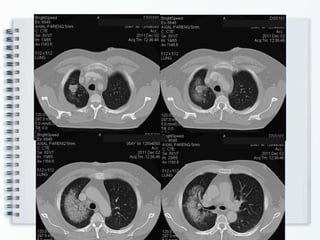

TAC tórax c/cte (2.12.11)

Disnea de esfuerzo. Hemoptisis 19.12.11 Lab: VSG 100. Citol normal. Uremia, creatininemia normal. Glucemia normal. BAAR – en 3 muestras. Perfil lipídico normal. Orina normal. Rx Tórax: No TAC tórax c/cte (2.12.11)